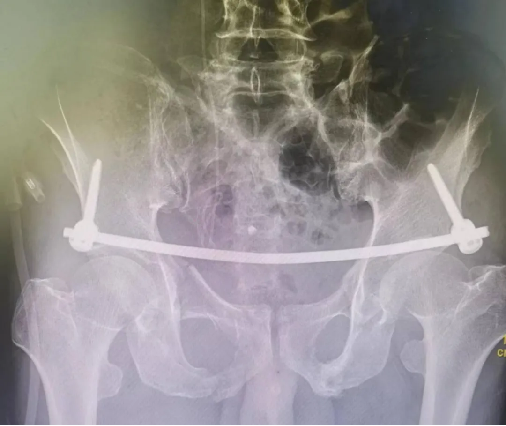

患者因外傷致骨盆前環骨折,患者難以忍(rěn)耐長期臥床及疼痛,要求(qiú)行手術治療以期早日自主翻身坐立活動。

骨盆前環微創經皮內固定技術(INFIX技術)固(gù)定結合了內固定和外固定的優點,揚長(zhǎng)避短,針對此類(lèi)患(huàn)者,有效避免了術後深部感染,又避(bì)免(miǎn)了使(shǐ)用外固(gù)定的手術並發症,讓患者在最佳(jiā)治療時機獲得了骨盆環的穩定,並能早期開始功能鍛煉,最大程度上降低了因傷致殘的機(jī)率。